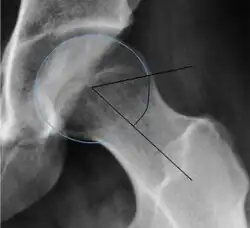

| Femoral head-neck offset | ![]() |

Offset of the femoral head with regard to most prominent aspect of the femora neck | >10 mm |

| Offset percentage | Femoral head-neck offset related to femoral head diameter | >0.18

| |